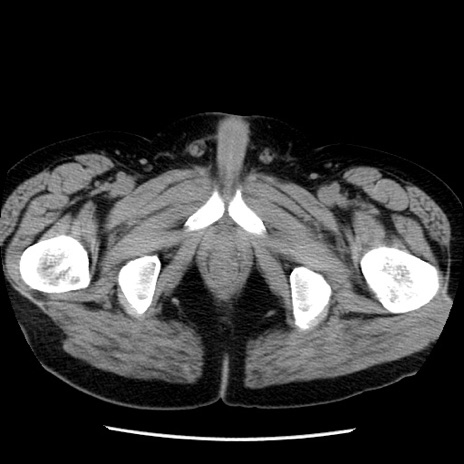

症例29(横断像)

【症例】40歳代男性

【現病歴】2日前から胃痛あり。徐々に周期的な激痛に変化した。本日になっても激痛があるため受診。

【身体所見】意識清明、BT 38-39℃台あり、腹部:膨満、やや硬、右下腹部に圧痛あり。

【データ】WBC 8500、CRP 23.26